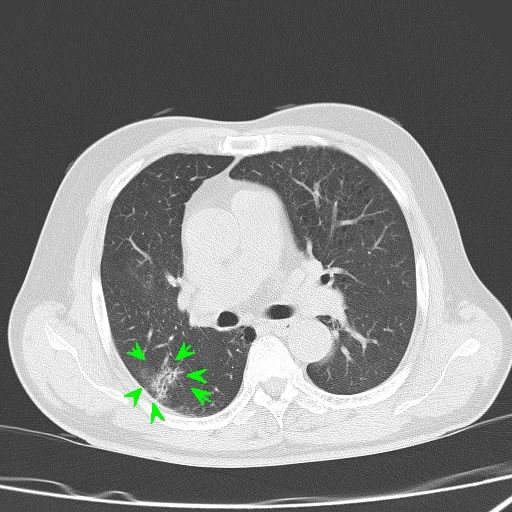

흉부 ctGGA 어떤건가요? 조금은 안심할수 있을까요?

폐 RUL 에 GGA 가 있다는 소견서를 받았습니다.

CT 이상소견 3~4CM 크기 신생불명

• 1번 째 사진